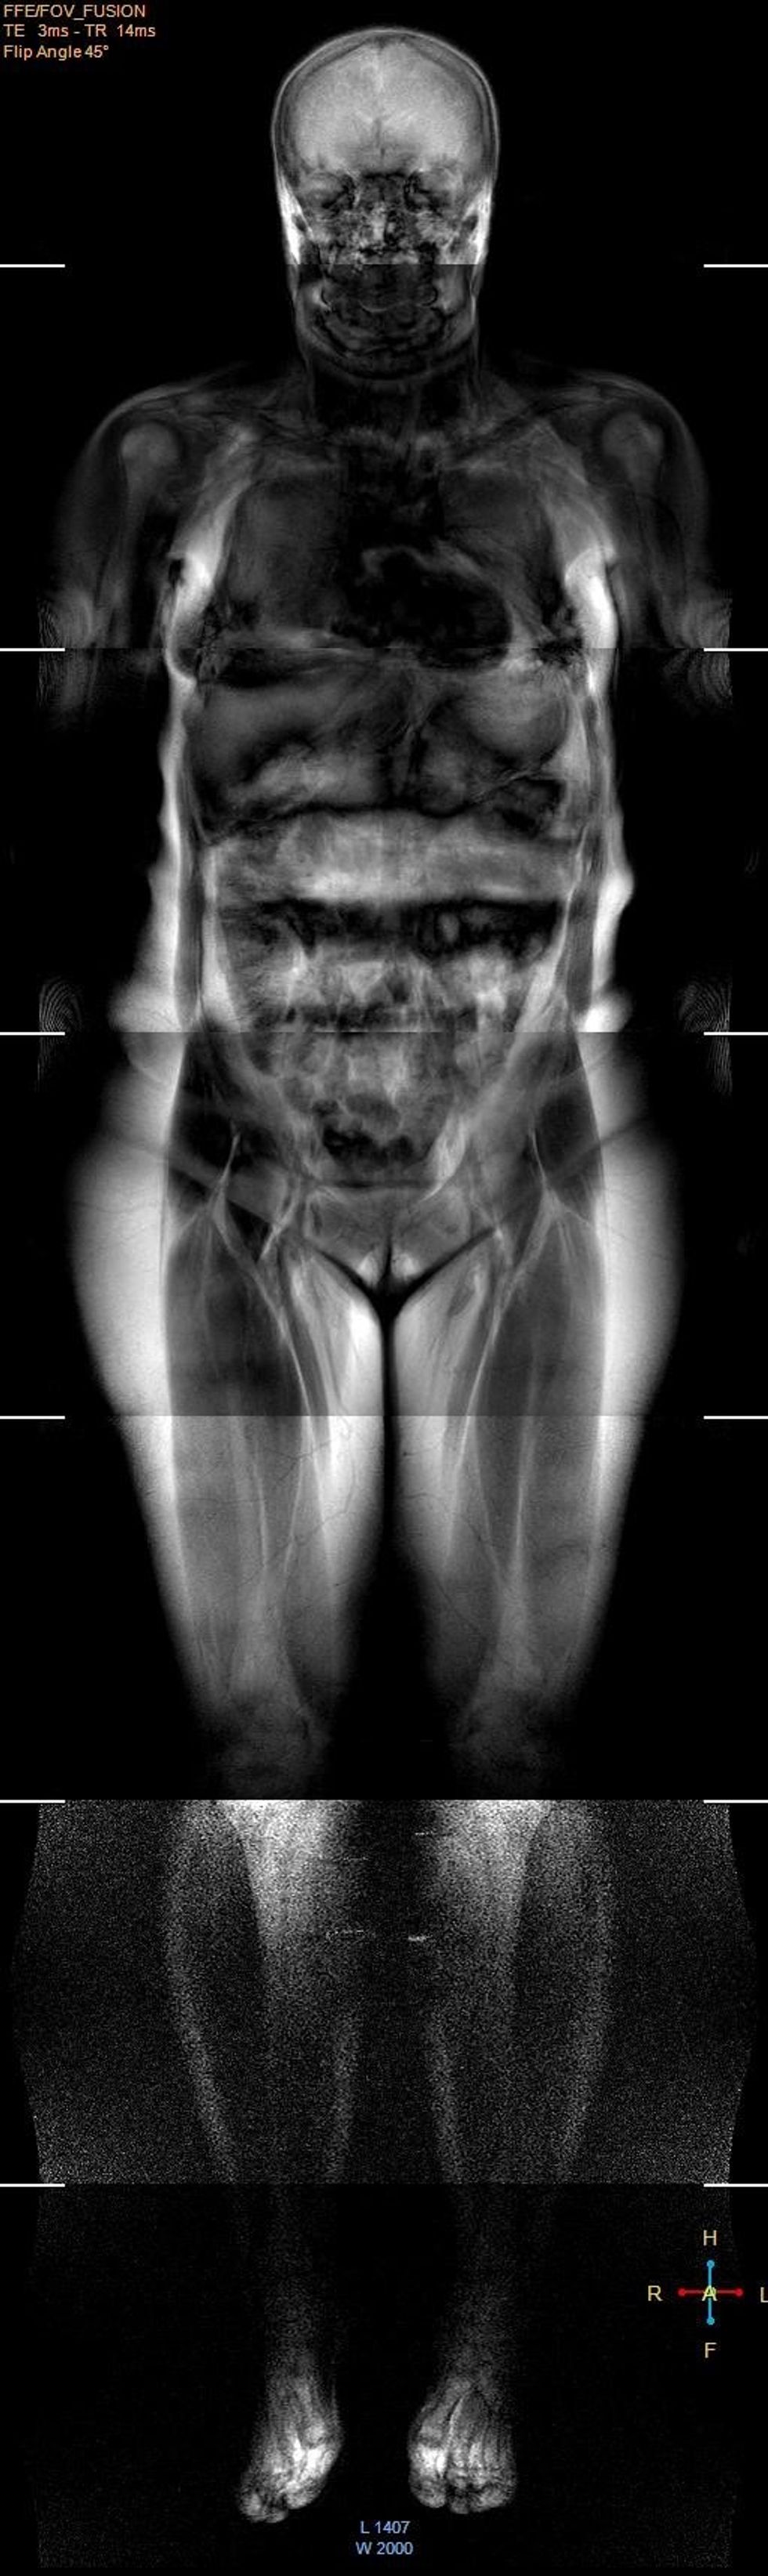

Në Klinikën e Radiologjisë të QKUK-së për herë të parë kryhet Rezonanca Magnetike e tërë trupit

Shërbimi Spitalor Klinik dhe Universitar i Kosovës ka njoftuar se në Klinikën e Radiologjisë të QKUK-së, është realizuar për herë të parë Rezonanca Magnetike e tërë trupit.

"Kompletimi i programeve softuerike, trajnimi i personelit dhe organizimi i shërbimeve tjera, mundësuan që të bëhet ky incizim i avancuar. Nevojat e popullatës dhe të klinicistëve për këtë incizim shumë të shtrenjtë, janë ekstremisht të mëdha dhe në të ardhmen planifikohet organizimi adekuat i këtij shërbimi për pacientët", thuhet në njoftim. /Telegrafi/